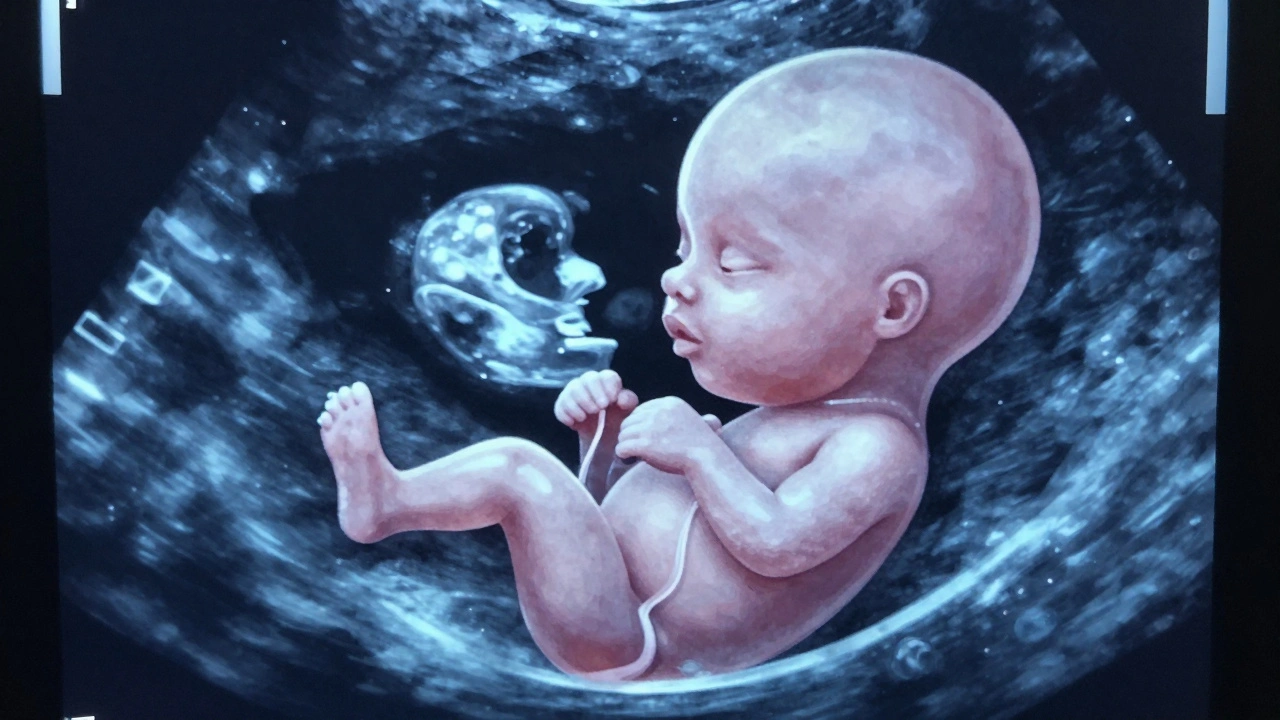

Na tomto ultrazvuku už můžete vidět, jak plod pije, jak se pohybuje, jak se kouká na vás - a to je moment, který si mnoho rodičů pamatuje celý život.

Vývoj plodu ve 8. týdnu s viditelnými začátky končetin a obličeje na ultrazvuku.